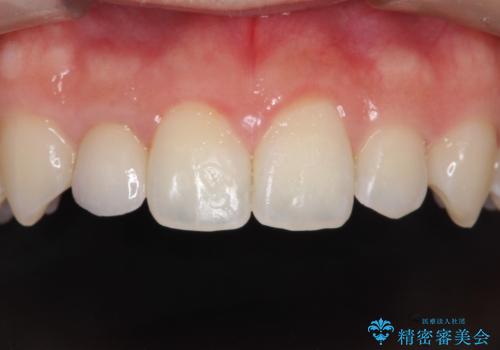

- 上の歯の隙間が気になるとのことで来院されました。

上顎の正中に隙間があり、右上の2番目の歯が通常の歯より小さい矮小歯でした。

正中の隙間をインビザライン矯正で閉鎖して、右上の2番目の歯にはセラミックを装着する計画としました。

矯正治療とセラミック治療を組み合わせることにより、審美的により良い結果を得ることができました。